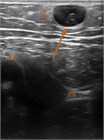

表在静脈の血栓症は,深部静脈血栓症と同じ危険因子や静脈瘤によって起こりうる.表在静脈血栓症が塞栓を起こすことはまれであるが,時間の経過とともに深部静脈系に及ぶことがあり,その際には塞栓のリスクははるかに高くなる.本章では,診断と管理について説明する.